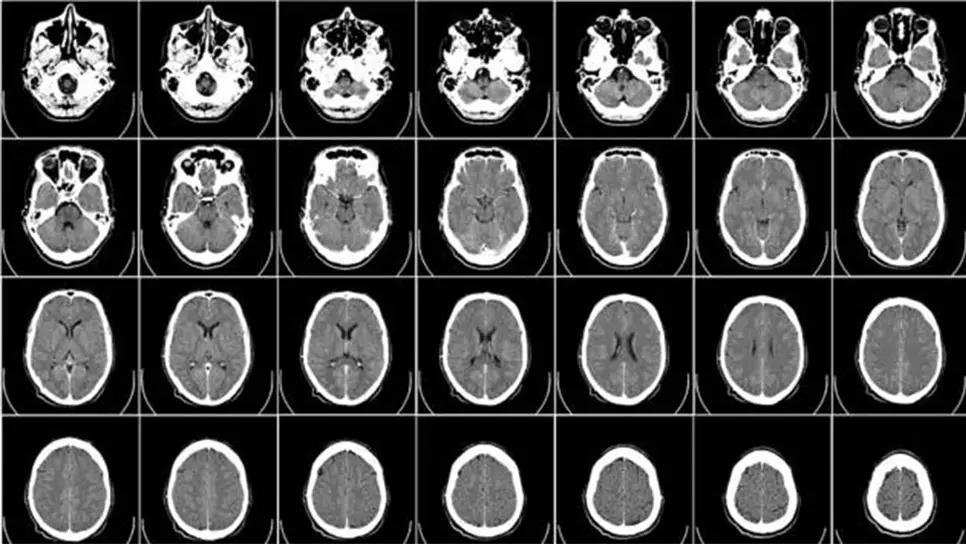

Asimismo, esta conexión funciona mediante una combinación de electroencefalogramas (EEG) para registrar los impulsos eléctricos que señalan la actividad del cerebro y la estimulación magnética transcraneal (EMT), donde ocurre una estimulación neuronal a través de campos magnéticos.